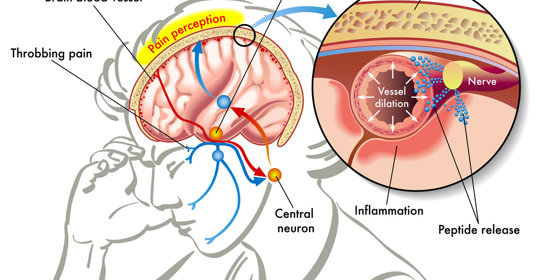

眶上神經痛:原因與治療

本文介紹了三義神經痛的原因以及可能涉及的相關疾病,如多發性硬化症、橋小腦角腫瘤、三叉神經炎或帶狀皰疹感染,並強調了針對特定原因進行針對性治療的重要性。該疾病常伴隨劇烈疼痛,因此藥物治療是必不可少的,若症狀持續未緩解,應儘快就醫以便獲得專業評估與治療。